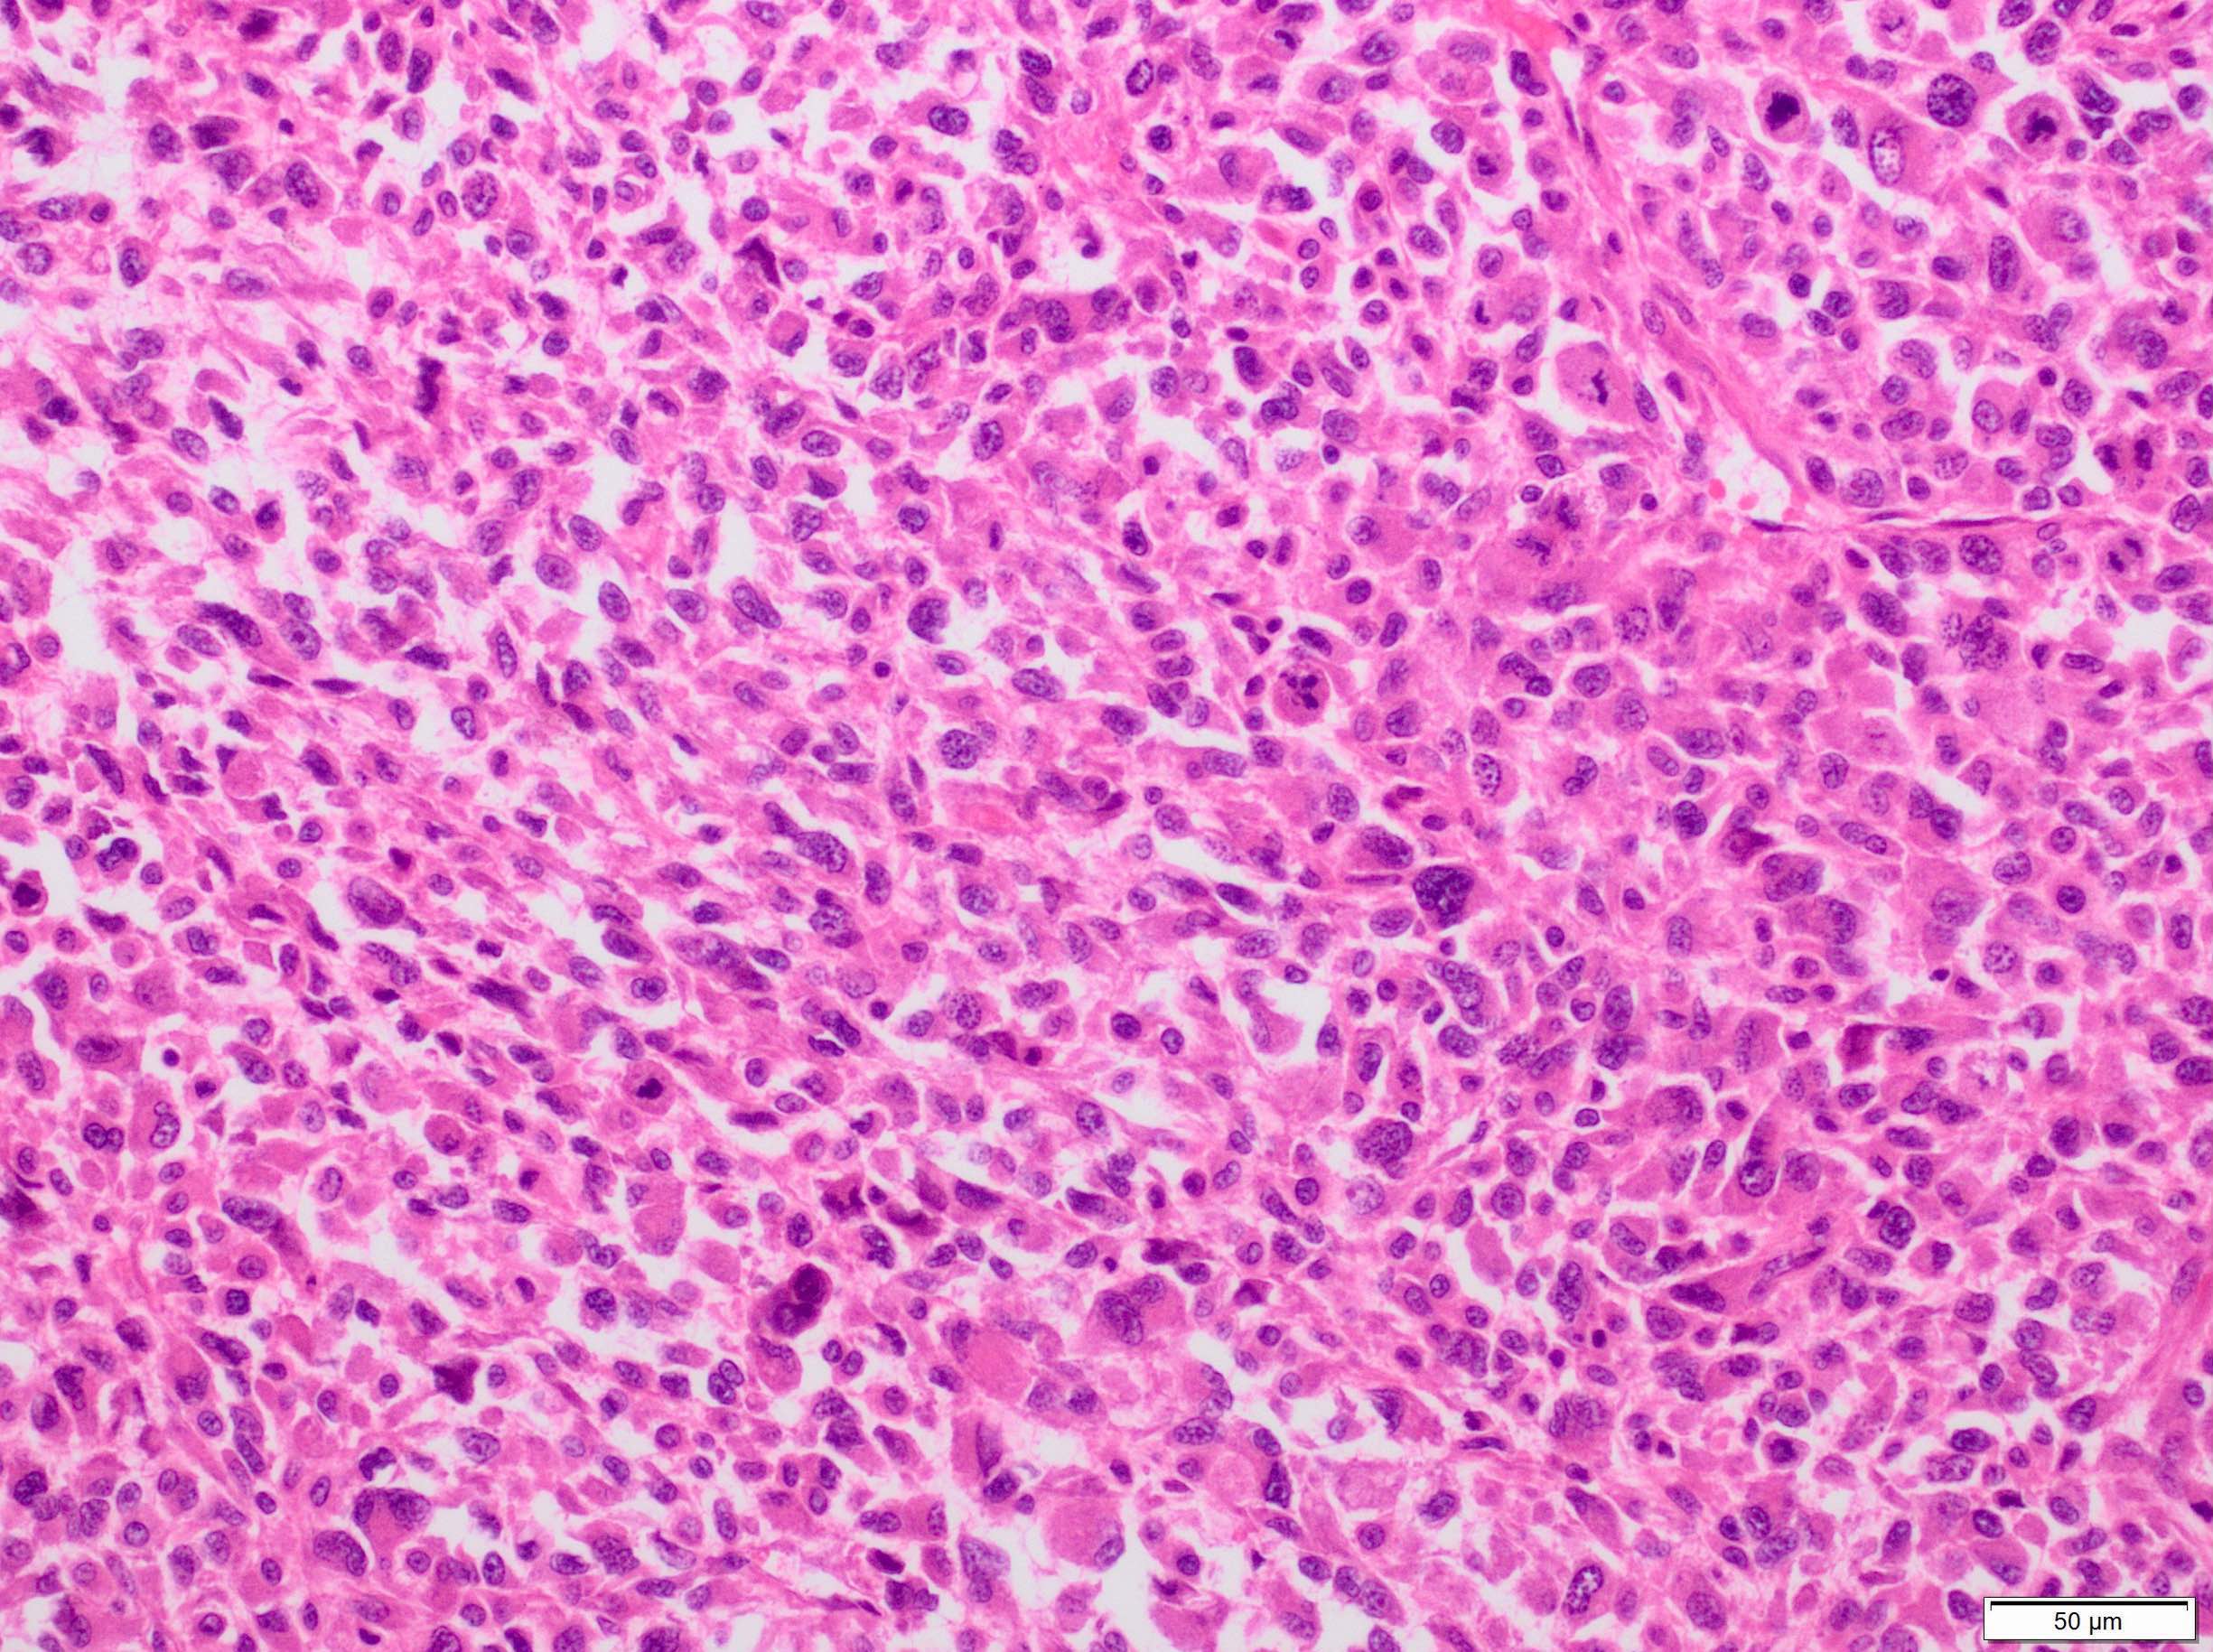

Microscopic (histologic) description

- Sheets of large, atypical and frequently multinucleated polygonal, spindled or rhabdoid eosinophilic cells (Am J Surg Pathol 2009;33:1850)

- Cross striations are seldom detected

Microscopic (histologic) images